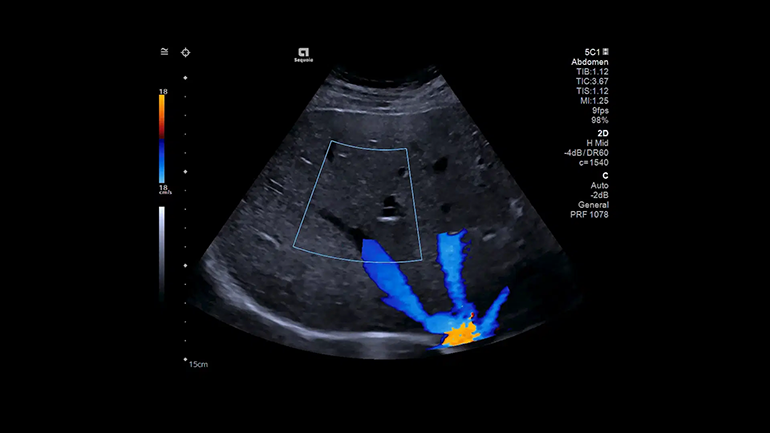

Технология улучшенного отображения просвета сосудов Clarify Vascular Enhancement

Технология Clarify Vascular Enhancement позволяет уменьшить количество артефактов, часто встречающихся на изображениях просвета сосудов и камер сердца плода, улучшает дифференцировку границ сосудов, позволяет значительно повысить качество визуализации сосудов малого диаметра.

Технология Slow Flow State

В технологии Slow Flow используются интеллектуальные фильтры, которые позволяют выделить кровеносные сосуды с помощью фильтрации движения, адаптивно улучшают ЭХО- сигнал и подавляют артефакты яркости. Эти интеллектуальные фильтры могут обнаруживать и маркировать низкоскоростной кровоток, который в противном случае был бы смешан с шумовыми артефактами и исключен из визуализации из-за скоростных ограничений, применяемых в обычном допплеровском режиме.